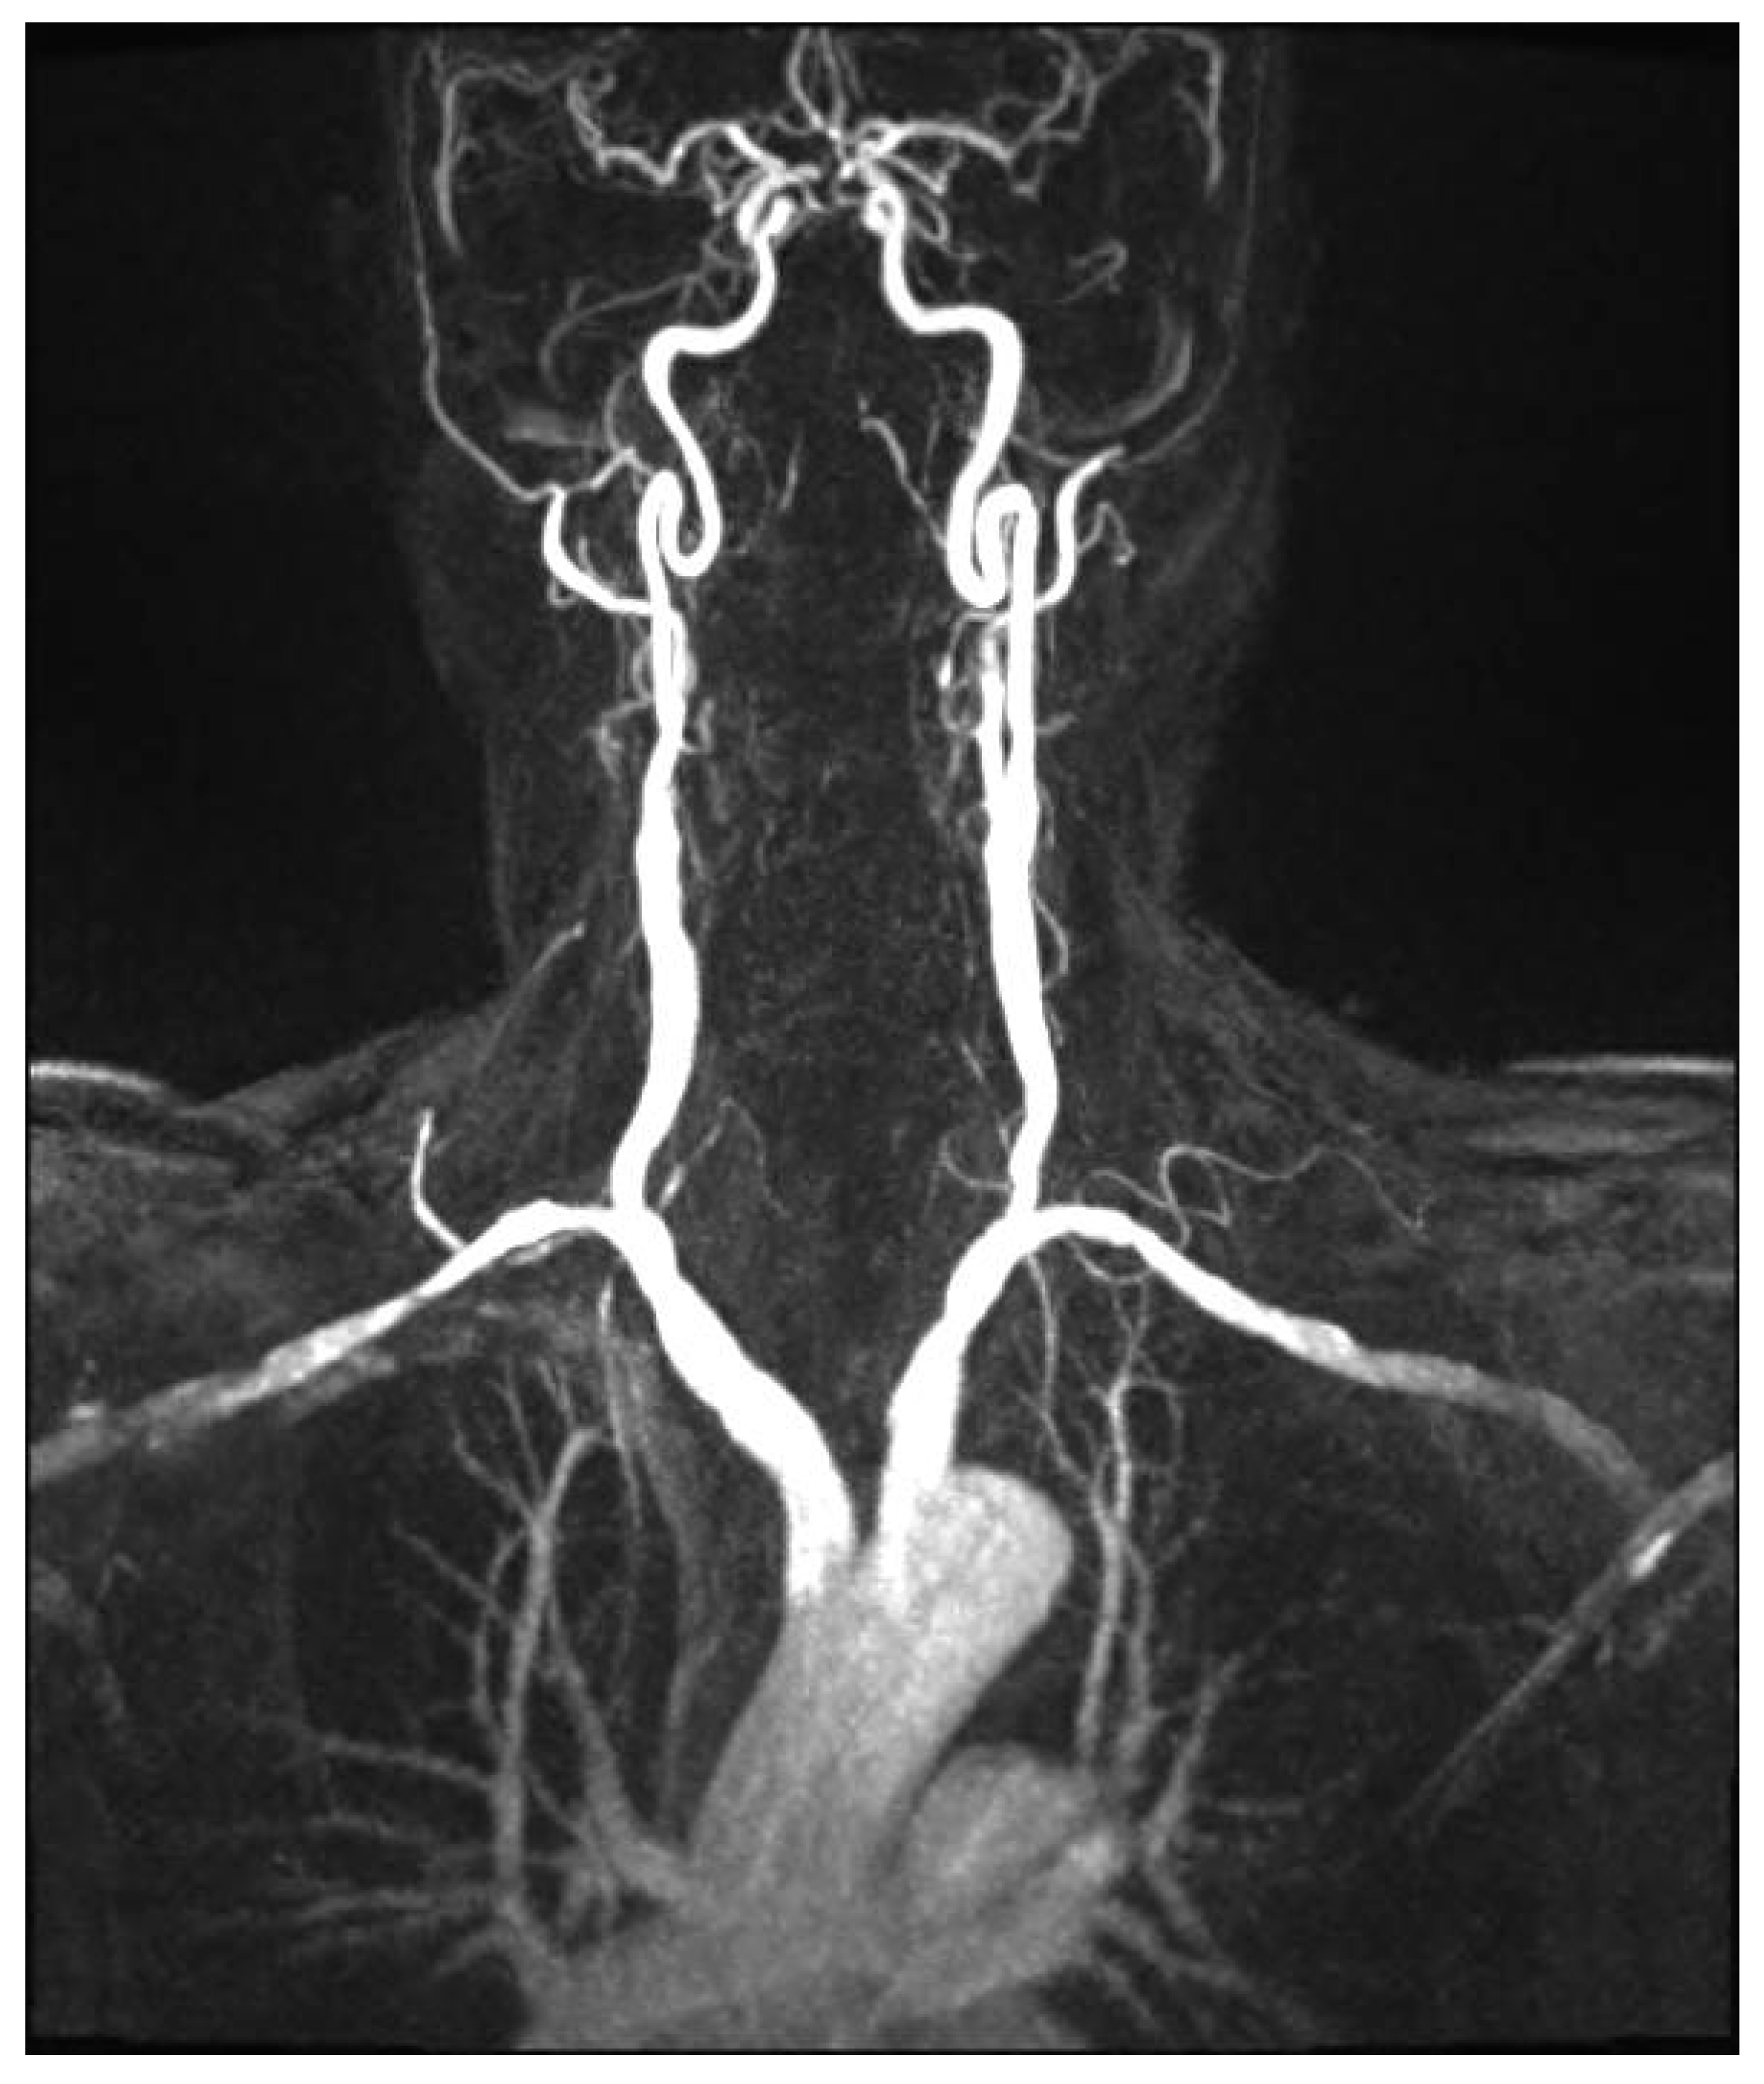

4.10.3. Cerebrovascular FMD

- Sethi, S.S.; Lau, J.F.; Godbold, J.; Gustavson, S.; Olin, J.W. The S curve: A novel morphological finding in the internal carotid artery in patients with fibromuscular dysplasia. Vasc. Med. 2014, 19, 356–362. [Google Scholar] [CrossRef]